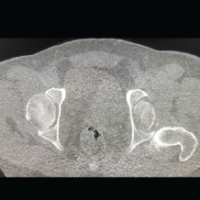

His complete blood picture and lipid profile were within normal limits, erythrocyte sedimentation rate was 20 mm/h, and uric acid level was 12.6 mg/dL. His serum homocysteine levels were elevated (21.38 umoL/L). Radiographs of both ankles showed soft tissue swelling in the region of tendoachilles without any bony involvement. Ultrasonography and magnetic resonance imaging showed well-defined soft tissue lesions along bilateral tendoachilles with well-circumscribed capsulated margins suggestive of tendoachilles xanthoma (Fig. 2). Fine needle aspiration cytology was performed and fluid from the nodular mass on the left heel was sent for biochemical analysis. Features consistent with Achilles tendon Xanthoma with gout were reported on histopathology and biochemical analysis. Patient was initially managed with analgesics, uric acid-lowering drugs, and ankle physiotherapy. As pain did not subside and the patient was uncomfortable while walking, he was planned for complete excision of the left tendoachilles xanthoma and reconstruction with ipsilateral FHL tendon transfer. Intraoperatively, the entire tendoachilles was bulky, nodular, and replaced by yellowish fat-like tissue from the musculotendinous junction to its insertion onto the calcaneum (Fig. 3). Complete excision of tendoachilles was performed (Fig. 4). Reconstruction of the tendoachilles was performed with the ipsilateral FHL tendon transfer with two-incision technique described by wiper (Fig. 5a, b, c, d). Histopathology showed tumor amidst fibromuscular tissue arranged in sheets composed of round to polygonal cells with round to oval nucleus and moderate to abundant amount of vacuolated cytoplasm and numerous multinucleated giant cells. Needle-shaped crystals were also seen. Features were consistent with the diagnosis of tendoachilles xanthoma along with gouty infiltration. Patient was given an above-knee plaster with ankle in 15° of plantar flexion for 8 weeks. Ankle ROM exercises and partial weight bearing were started at 8 weeks. Gradual strengthening exercises and full weight bearing were allowed at 12 weeks. Interim follow-up was done at 6 months, 1 year and at final follow-up after 3 years (before submission of the manuscript) there was no recurrence observed, patient could walk normally and could stand on tip toes on the operated limb (Fig. 6). Patient was so comfortable with the surgery and the outcome that he could manage his activities with the operated limb despite the presence of tendon xanthoma on the contralateral side for which a similar procedure is due.